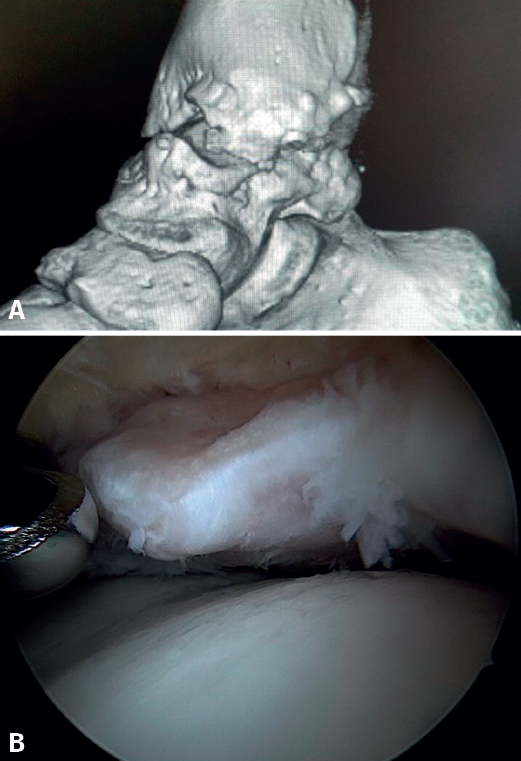

Anterior ankle impingement is defined as pain and/or limitation of range of motion that occurs with dorsiflexion of the ankle, due to the presence of soft tissue or bone interposed between the joint surfaces. A distinction is made between soft tissue impingement (synovial proliferation, thickening of Bassett's ligament, capsular adhesions), bony impingement (osteophytes or alterations in the ankle or hindfoot axis) (Figure 1) and mixed impingement (Table 1). AAI in turn can be subdivided into central, anterolateral and anteromedial impingement(8), with the first two being the most common presentations(9). Anterolateral AAI usually involves soft tissue, while anteromedial AAI is usually caused by a spatial conflict between osteophytes of the talar neck and anterior to the medial malleolus in dorsiflexion(9,10). AAI is the most common cause of anterior ankle pain that worsens with dorsiflexion. However, posterior impingement may be more frequent in certain patient groups, such as dancers or football players, due to repetitive movements in forced plantar flexion(4).

Bony AAI due to osteophytes has also been linked to the presence of chronic instability. It has been postulated that altered joint kinematics secondary to ligament insufficiency favors the development of osteophytes in the anterior region of the tibia and talus(36,37). Recent studies have questioned the theory of repeated capsular traction as the origin of osteophytes in sports(38), as it is easily demonstrated that osteophytes are located intra-articular within the capsular insertion, in the context of ankle arthroscopy (Figure 2). Therefore, ankle dorsiflexion arthroscopy is essential to safely resect osteophytes without damage to the capsule or overlying structures, whereas the classical traction technique (invasive or otherwise) would make resection extremely difficult, and is thus not recommended nowadays for routine use(3,39). Vega distinguished between two types of osteophytes(3), according to whether they are caused by repetitive trauma (peak-shaped) or instability (visor-shaped). The concept of micro-instability is associated with repetitive micro-trauma, which could be the origin of osteophytes with this characteristic morphology (Figure 3).